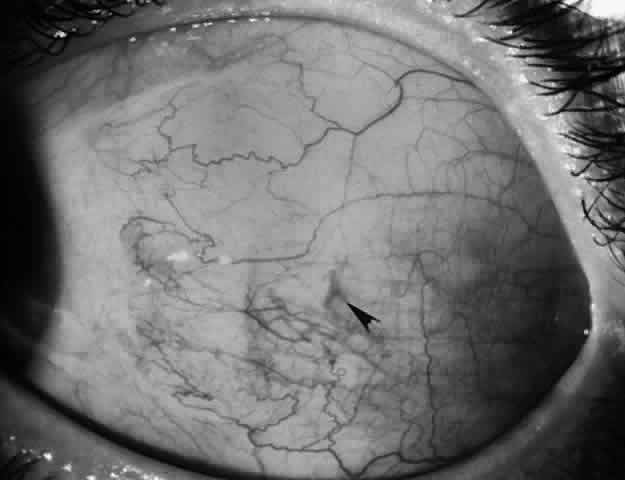

Whenever possible, efforts should be made to obtain information from the patient's history and from clinical records regarding the original diagnosis, preoperative measurements, and previous surgical procedures. In lieu of this information, some information can be obtained on examination. For example, slit lamp examination may disclose conjunctival scarring, which may suggest which muscles have had prior surgery (Fig. 7).

Fig. 7. Conjunctival scarring over the lateral rectus muscle and the history of correction of an exotropia suggest that the lateral rectus muscle had been recessed.